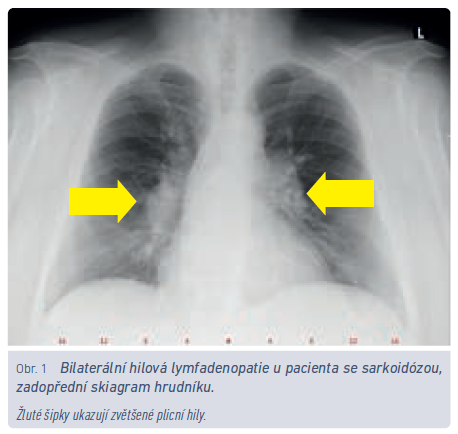

Roční incidence sarkoidózy v ČR je udávána 3,1/100 000 obyvatel, prevalence světově 6–23,1/100 000 obyvatel.8 Pro srovnání, prevalence chronické obstrukční plicní nemoci (CHOPN) v roce 2017 v ČR byla 21,6/1 000 obyvatel.9 Zatímco pacientů s CHOPN je tedy v ČR zhruba čtvrt milionu, nemocných se sarkoidózou může být 600–2 300. V případě akutního rozvoje sarkoidózy v podobě výše uvedeného Löfgrenova syndromu je velmi pravděpodobné, že onemocnění vymizí samo, bez nutnosti systematické léčby (obr. 1). Dominantním problémem u této skupiny nemocných bývá erythema nodosum v oblasti bérců a velmi často otoky a bolest kotníků. Nezřídka bývají nemocní léčeni antibiotiky (záměna s poštípáním hmyzem), odesíláni na kožní oddělení nebo k revmatologovi. Charakteristický nález bilaterální hilové lymfadenopatie společně s erythema nodosum pro diagnózu postačí, a je‑li propuknutí nemoci provázeno i systémovými příznaky (subfebrilie, febrilie), není pro stanovení diagnózy požadována histologická verifikace. Jsou‑li nemocnému v této fázi podány symptomaticky systémové kortikosteroidy, zvyšuje se riziko jak recidiv, tak přechodu do chronické formy.10